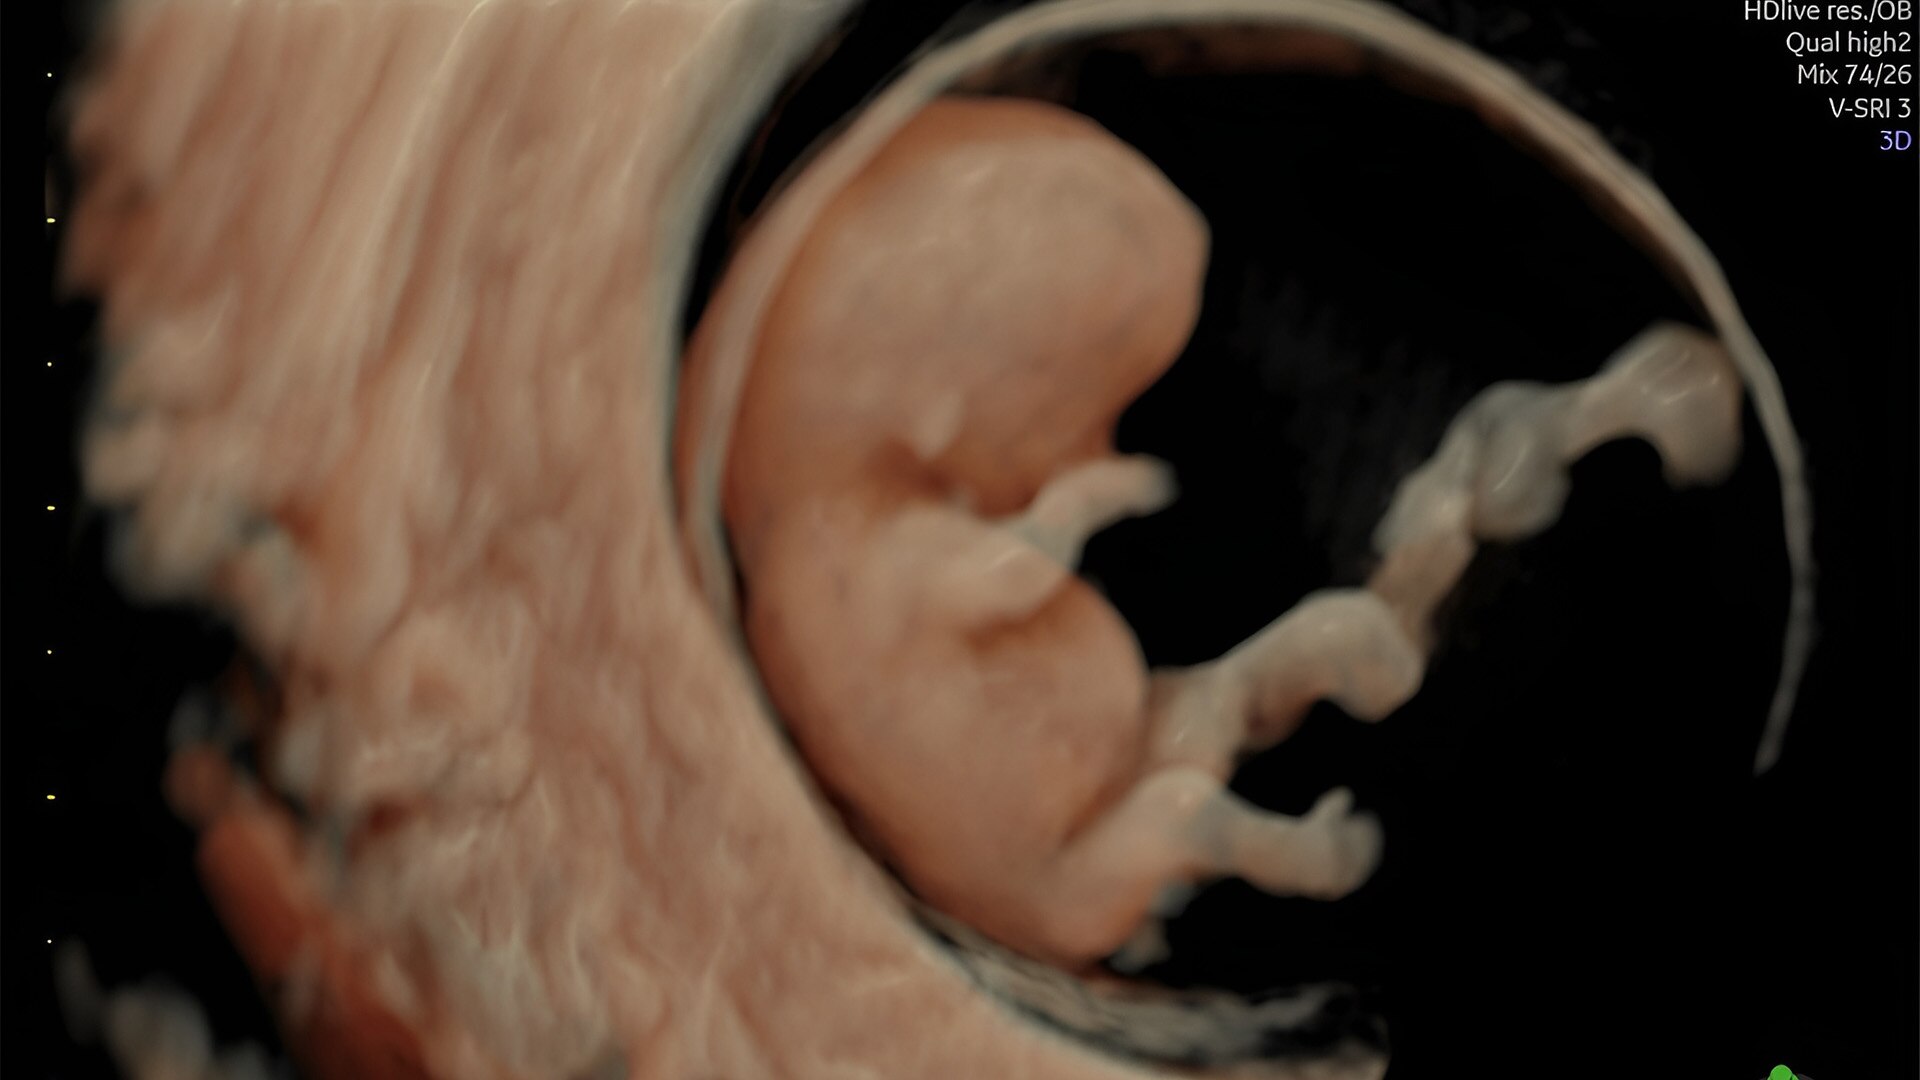

First trimester exams

Perform detailed exams with high-resolution for early insights to fetal health

Fetal heart evaluation

Get to the heart of the matter

Identifying fetal cardiac abnormalities earlier means you can intervene sooner, plan for delivery, and potentially improve outcomes. The Voluson Expert 22 provides a full solution of progressive tools, to help distinguish the tiniest structures with stunning clarity to provide patient answers faster.